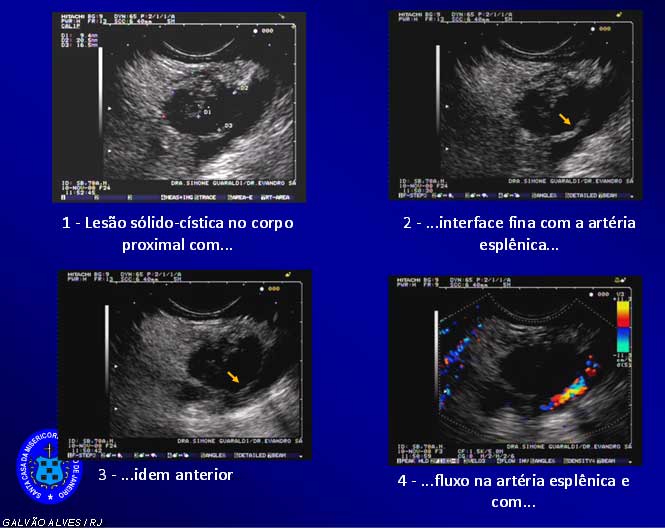

optamos por Ecoendoscopia ( figuras 4e 5) que identificou lesão expansiva do corpo pancreático proximal, confirmou trombose de esplênica e a biopsia da massa mostrou adenocarcinoma moderadamente diferenciado com padrão mucosecretor. O estudo bioquímico da secreçāo pancreática mostra CA 19.9 e CEA ELEVADOS compatíveis com neoplasia .

Figura 4 – Ecoendoscopia

Figura 5 – Ecoendoscopia + Biópsia e Histopatologia

A avaliação por imagem mostra a pancreatite através da calcificação do orgão e as tromboses para -neoplásicas mas não o tumor propriamente .A ecoendoscopia confirma os achados , mostra o tumor no corpo , realiza estudo bioquímico e permite a histopatologia diagnostica de adenocarcinoma.